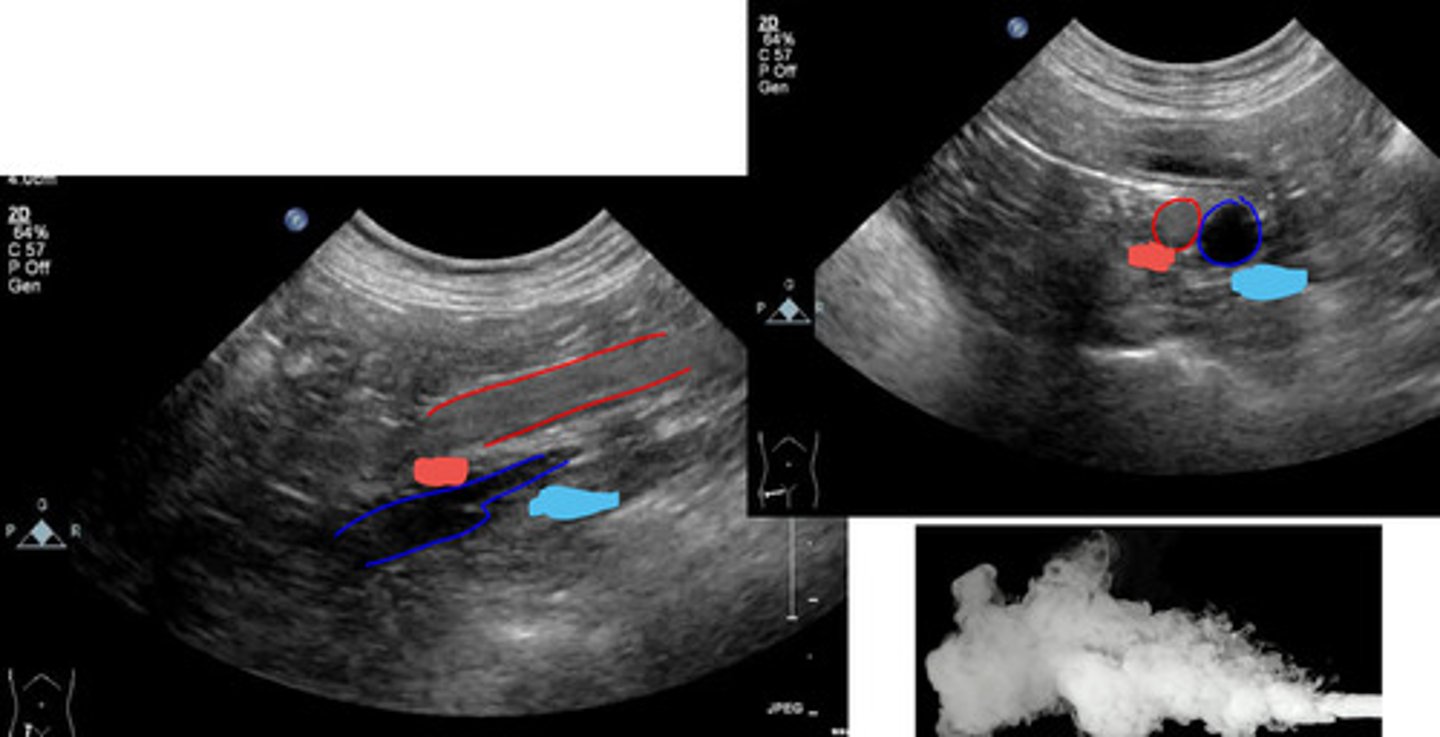

red- external iliac a.

blue- internal iliac a.

ID red and blue arrows (aortic trifurcation)

red- vena cava

blue- aorta

red- right side of body

blue- left side of body

orientation- transverse b/c round

ID red and blue, which one is on the right side of the body and which is on the left? what orientation is this?